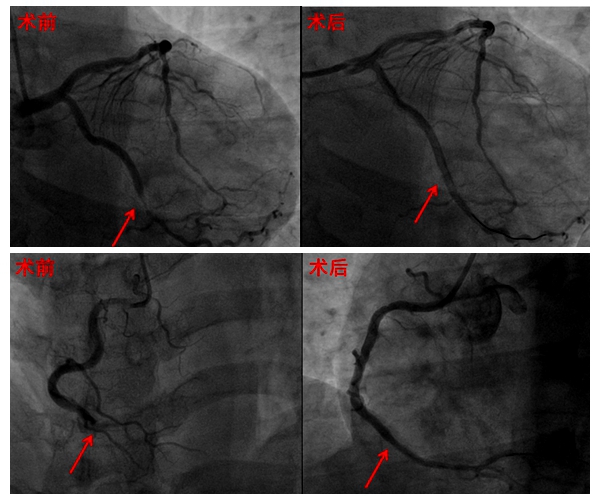

完善冠脉造影示:右冠动脉远段闭塞伴血栓影,回旋支近中段局限性狭窄90%,远段血流减慢。最终在右冠及回旋支病变处分别植入支架一枚,术后支架内未见残留狭窄,远端血流恢复。

术后,患者恢复良好,胸痛改善,心绞痛未再发作,自觉症状明显改善。